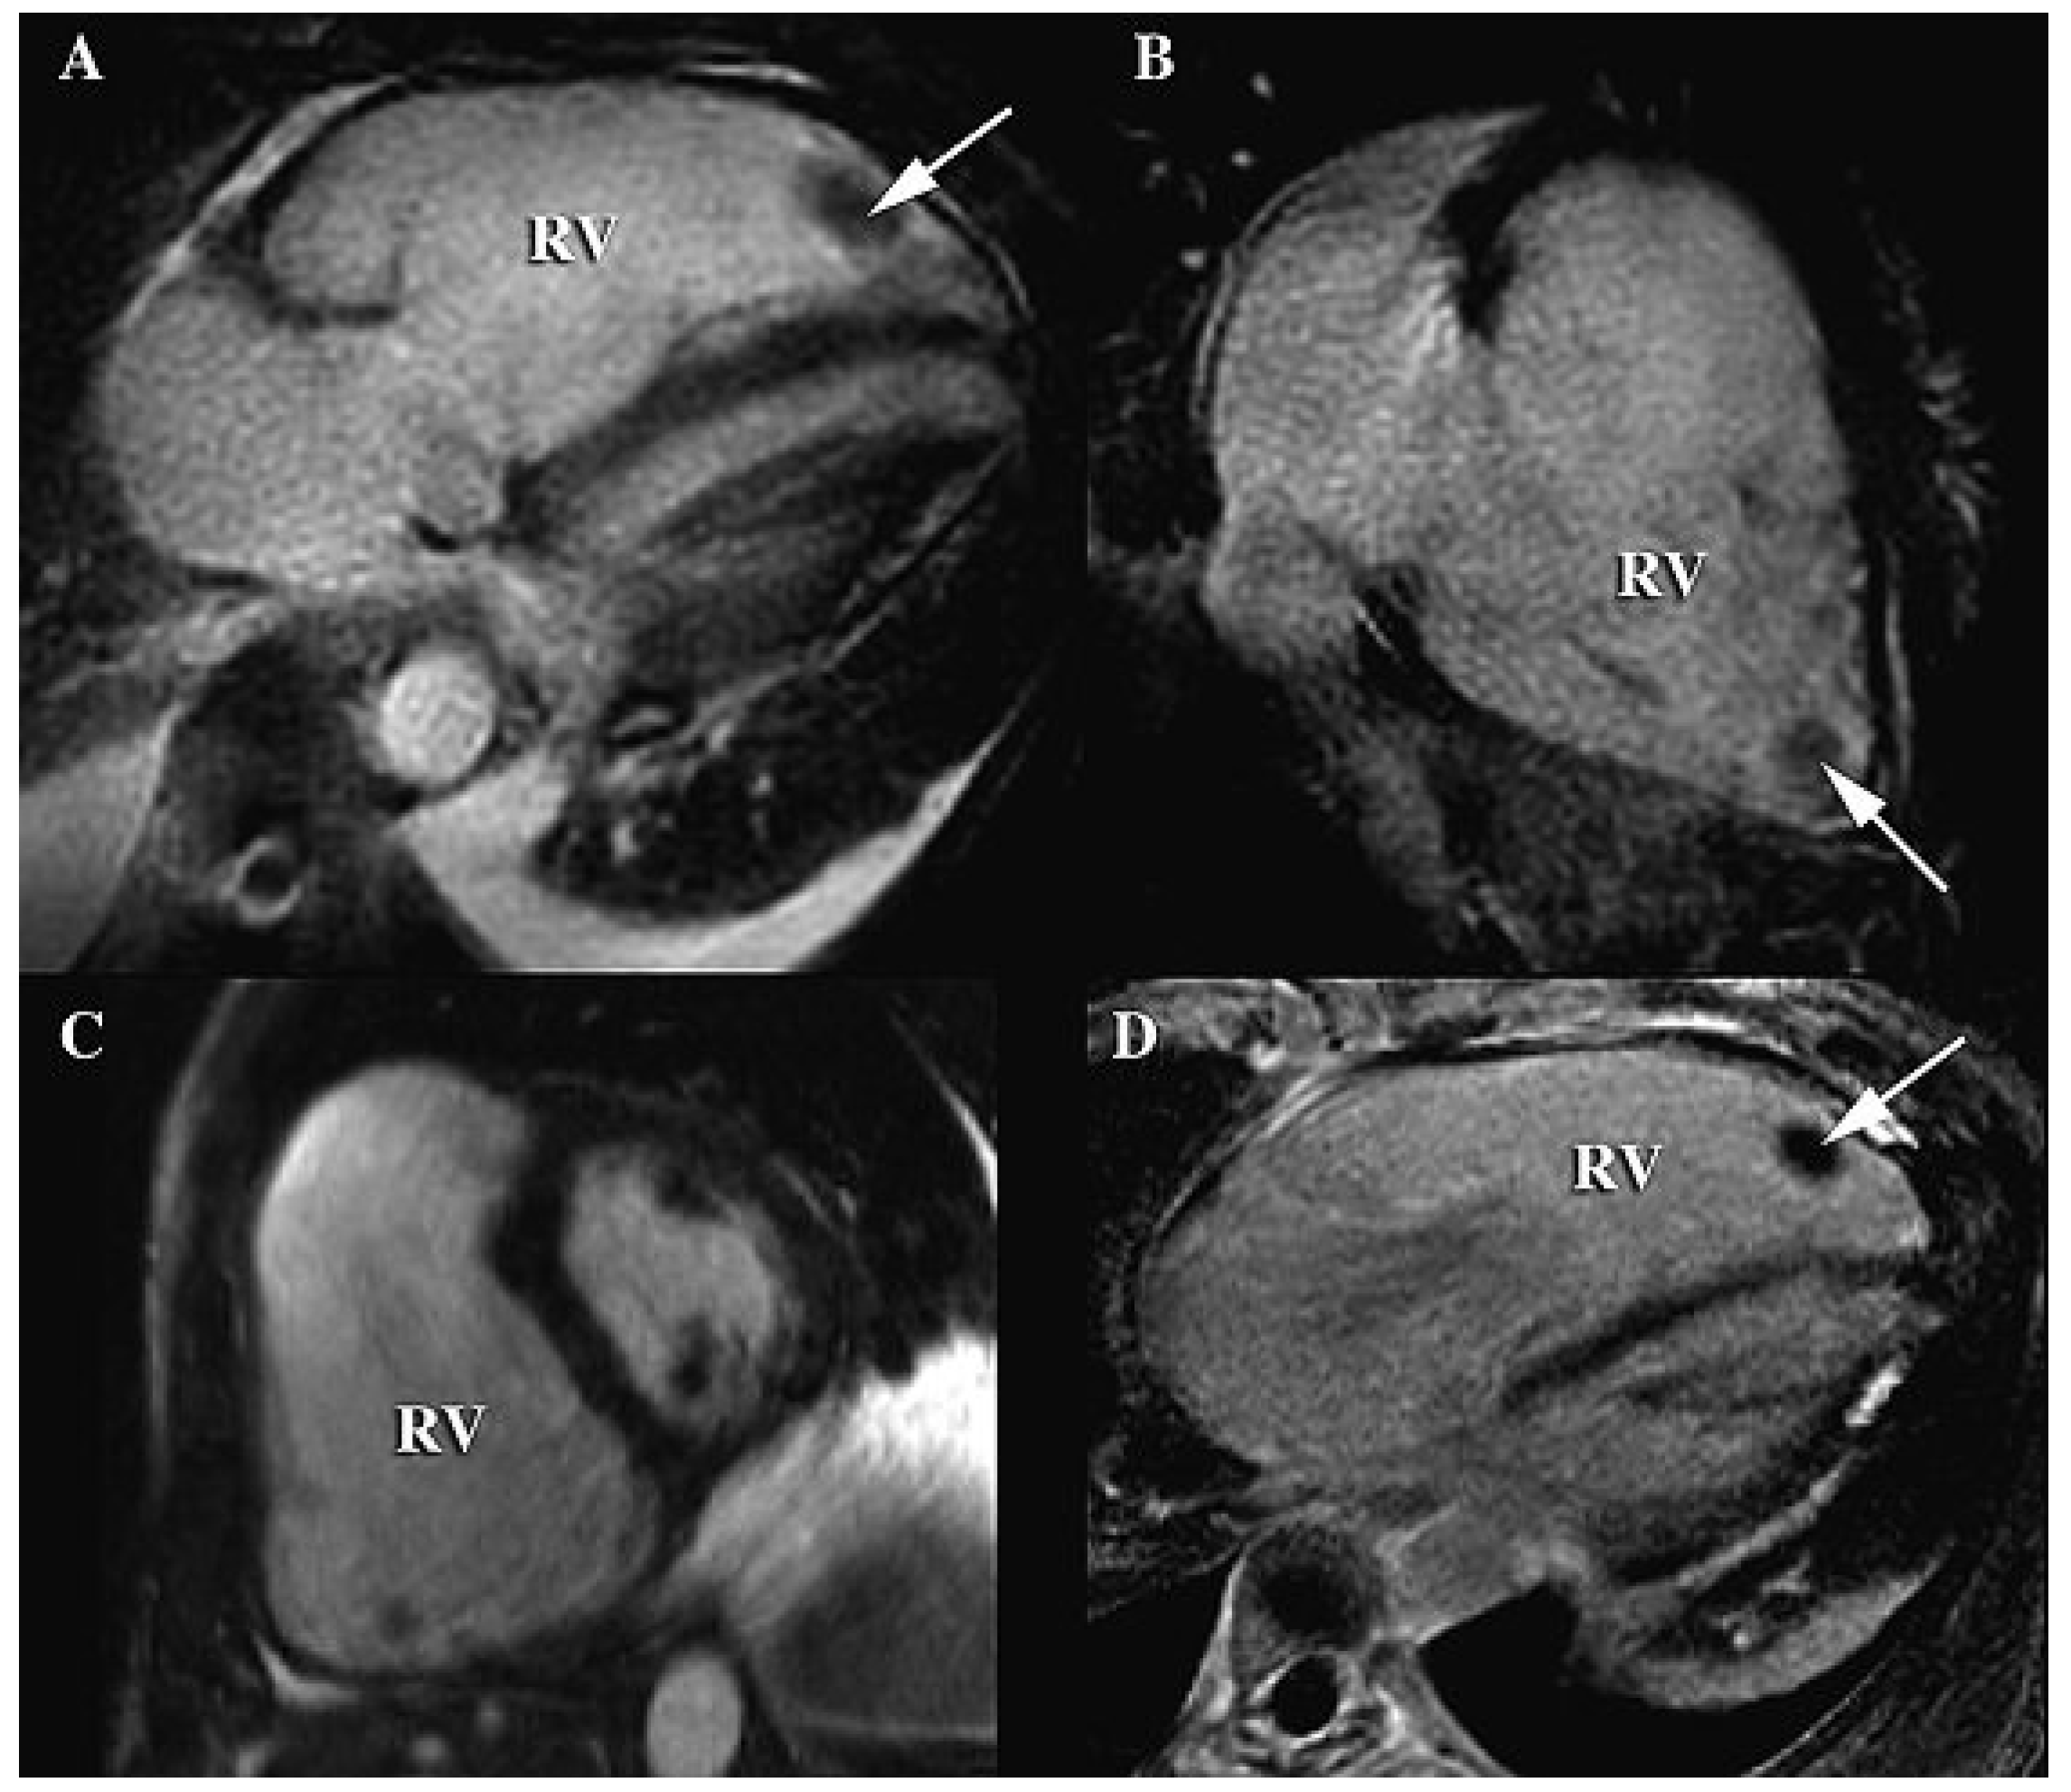

Figure 3.

Cardiac magnetic resonance imaging; cine SSFP sequences in four-chamber (A), two-right-chamber (B) and short-axis (C) views showing massive dilatation of the right ventricle (RV) with global thinning of the anterior wall and a severely diminished ejection fraction (20%). Paradoxical motion of the interventricular septum was also demonstrated, with protrusion of the septum towards the left ventricle, clearly visible during early diastole on C. The small thrombus at the apex of the RV seen on the CT-scan was also present (arrows) and was particularly visible on the late-enhancement (PSIR) sequence in the four-chamber view (D).

Along with the clinical events, ECG and echocardiographic findings, cardiac magnetic resonance imaging (Figure 3) and single-averaged ECG confirmed the diagnosis of ARVC. The subsequent hospital stay was marked by full haemodynamic and neurological recovery, and the patient received an implantable cardioverter-defibrillator. She was discharged on betablockers, angiotensin-converting enzyme inhibitors and anticoagulation therapy.

The present case is remarkable for several features. First and foremost is the extremely severe extent of the ARVC in this patient, with massive dilatation of the right ventricle and also involvement of the left ventricle. Moreover, this translated into a caricatural aspect of the ECG, with giant epsilon waves and T wave inversion in all precordial leads. Finally, the patient was admitted with pulmonary embolism, which is a rare but known complication of ARVC [7]. The emboli most certainly originated from the RV thrombus, and possibly contributed to triggering the ventricular arrhythmia due to the sudden increase in afterload in an already impaired RV. Alternatively, the thrombus may have migrated to the lungs following CPR and electric defibrillation, after ventricular fibrillation solely secondary to the ARVC. Of note, the CT scan showed only segmentary pulmonary embolism, but was performed after the administration of thrombolysis, which probably dissolved most of the emboli and therefore possibly led to underestimation of the initial extent of the embolic event.